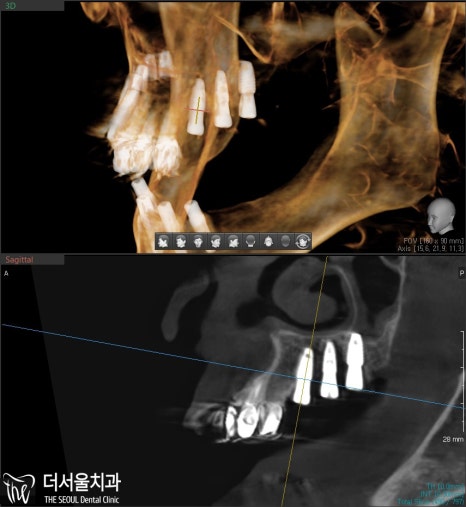

수술을 진행하기 앞서

CBCT와 네비게이션 가이드를 이용하여

정밀 검사를 선행해줍니다.

산성역치과 에서 확인한 결과,

전반적으로 골폭이 좁은 상태였습니다.

픽스처를 심는다 하더라도

튼튼한 고정력을 갖추기 어렵습니다.

때문에 뼈이식을 진행하기로 합니다.

픽스처를 심을 수 있을 정도로

깊이는 충분했습니다.

그러나 옆을 보면 폭은 충분치 않죠.

따라서 옆 부분에 뼈 재료를

아낌없이 넣어드려서

두꺼운 골폭을 형성했습니다.